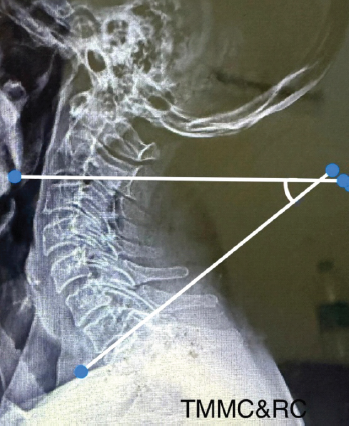

This prospective and cross-sectional study was conducted in the orthopaedic department of a tertiary health care center. The study included 255 adult patients with age above 18 years of either gender with neck pain attending the outpatient department during December 2023 till May 2025. The study was conducted after approval from the College research committee (CRC) and Institutional Ethics Committee (IEC) (approval no.: TMU/IEC No. 23/116). A written informed consent was obtained from all subjects. Our study is a cross-sectional study (level IV evidence). The study was carried out as per the standards laid down in the Helsinki Declaration (1964) and its amendment (2013). The patients were stratified into three groups. Neck pain cases without radiation to upper limb were categorised as group I, those with radiation to upper limb as group II and those with neck pain with radiculopathy/ myelopathy as group III. Patients with a history of trauma, previous surgery, inflammatory or infective pathology, degenerative joint disease and congenital conditions of the cervical spine or shoulder were excluded. Patients were evaluated by detailed history taking, examination and relevant investigations. A standard lateral radiograph of cervical spine was done in a comfortable standing position with upper extremities positioned naturally at the side of body, maintaining horizontal gaze. Cobb’s angle (C2-C7) and Jackson physiological stress (JPS) angle was measured on a plain radiograph in lateral view of cervical spine using DICOM software, by a radiologist who was blinded to clinical findings. The Cobb’s angle was measured as the angle between the tangential line inferior endplate of the second vertebra (C2) and another line tangential to the inferior end plate of seventh vertebra (C7) (Figure 1 ) [10]. The Jackson physiological stress angle was measured between drawing a tangential line on the posterior surface of the second cervical vertebra (C2) and another tangential line drawn on the posterior surface of seventh cervical vertebra (C7). The angle of intersection between these two lines is Jackson physiological stress (JPS) angle (Figure 2) [10]. Both angles were measured using lateral radiographs and DICOM software, allowing for precise calculations. MRI Cervical spine was done to confirm the diagnosis of Radiculopathy/ myelopathy if needed.

Figure 1: The Cobb angle is measured as the angle between the tangent on the inferior endplate of the second vertebra (C2) and the tangent on the inferior endplate of the seventh vertebra (C7).

Figure 2: The Jackson physiological stress angle is measured between the tangent on the posterior surface of the second cervical vertebra (C2) and the tangent on the posterior surface of the seventh cervical vertebra (C7).